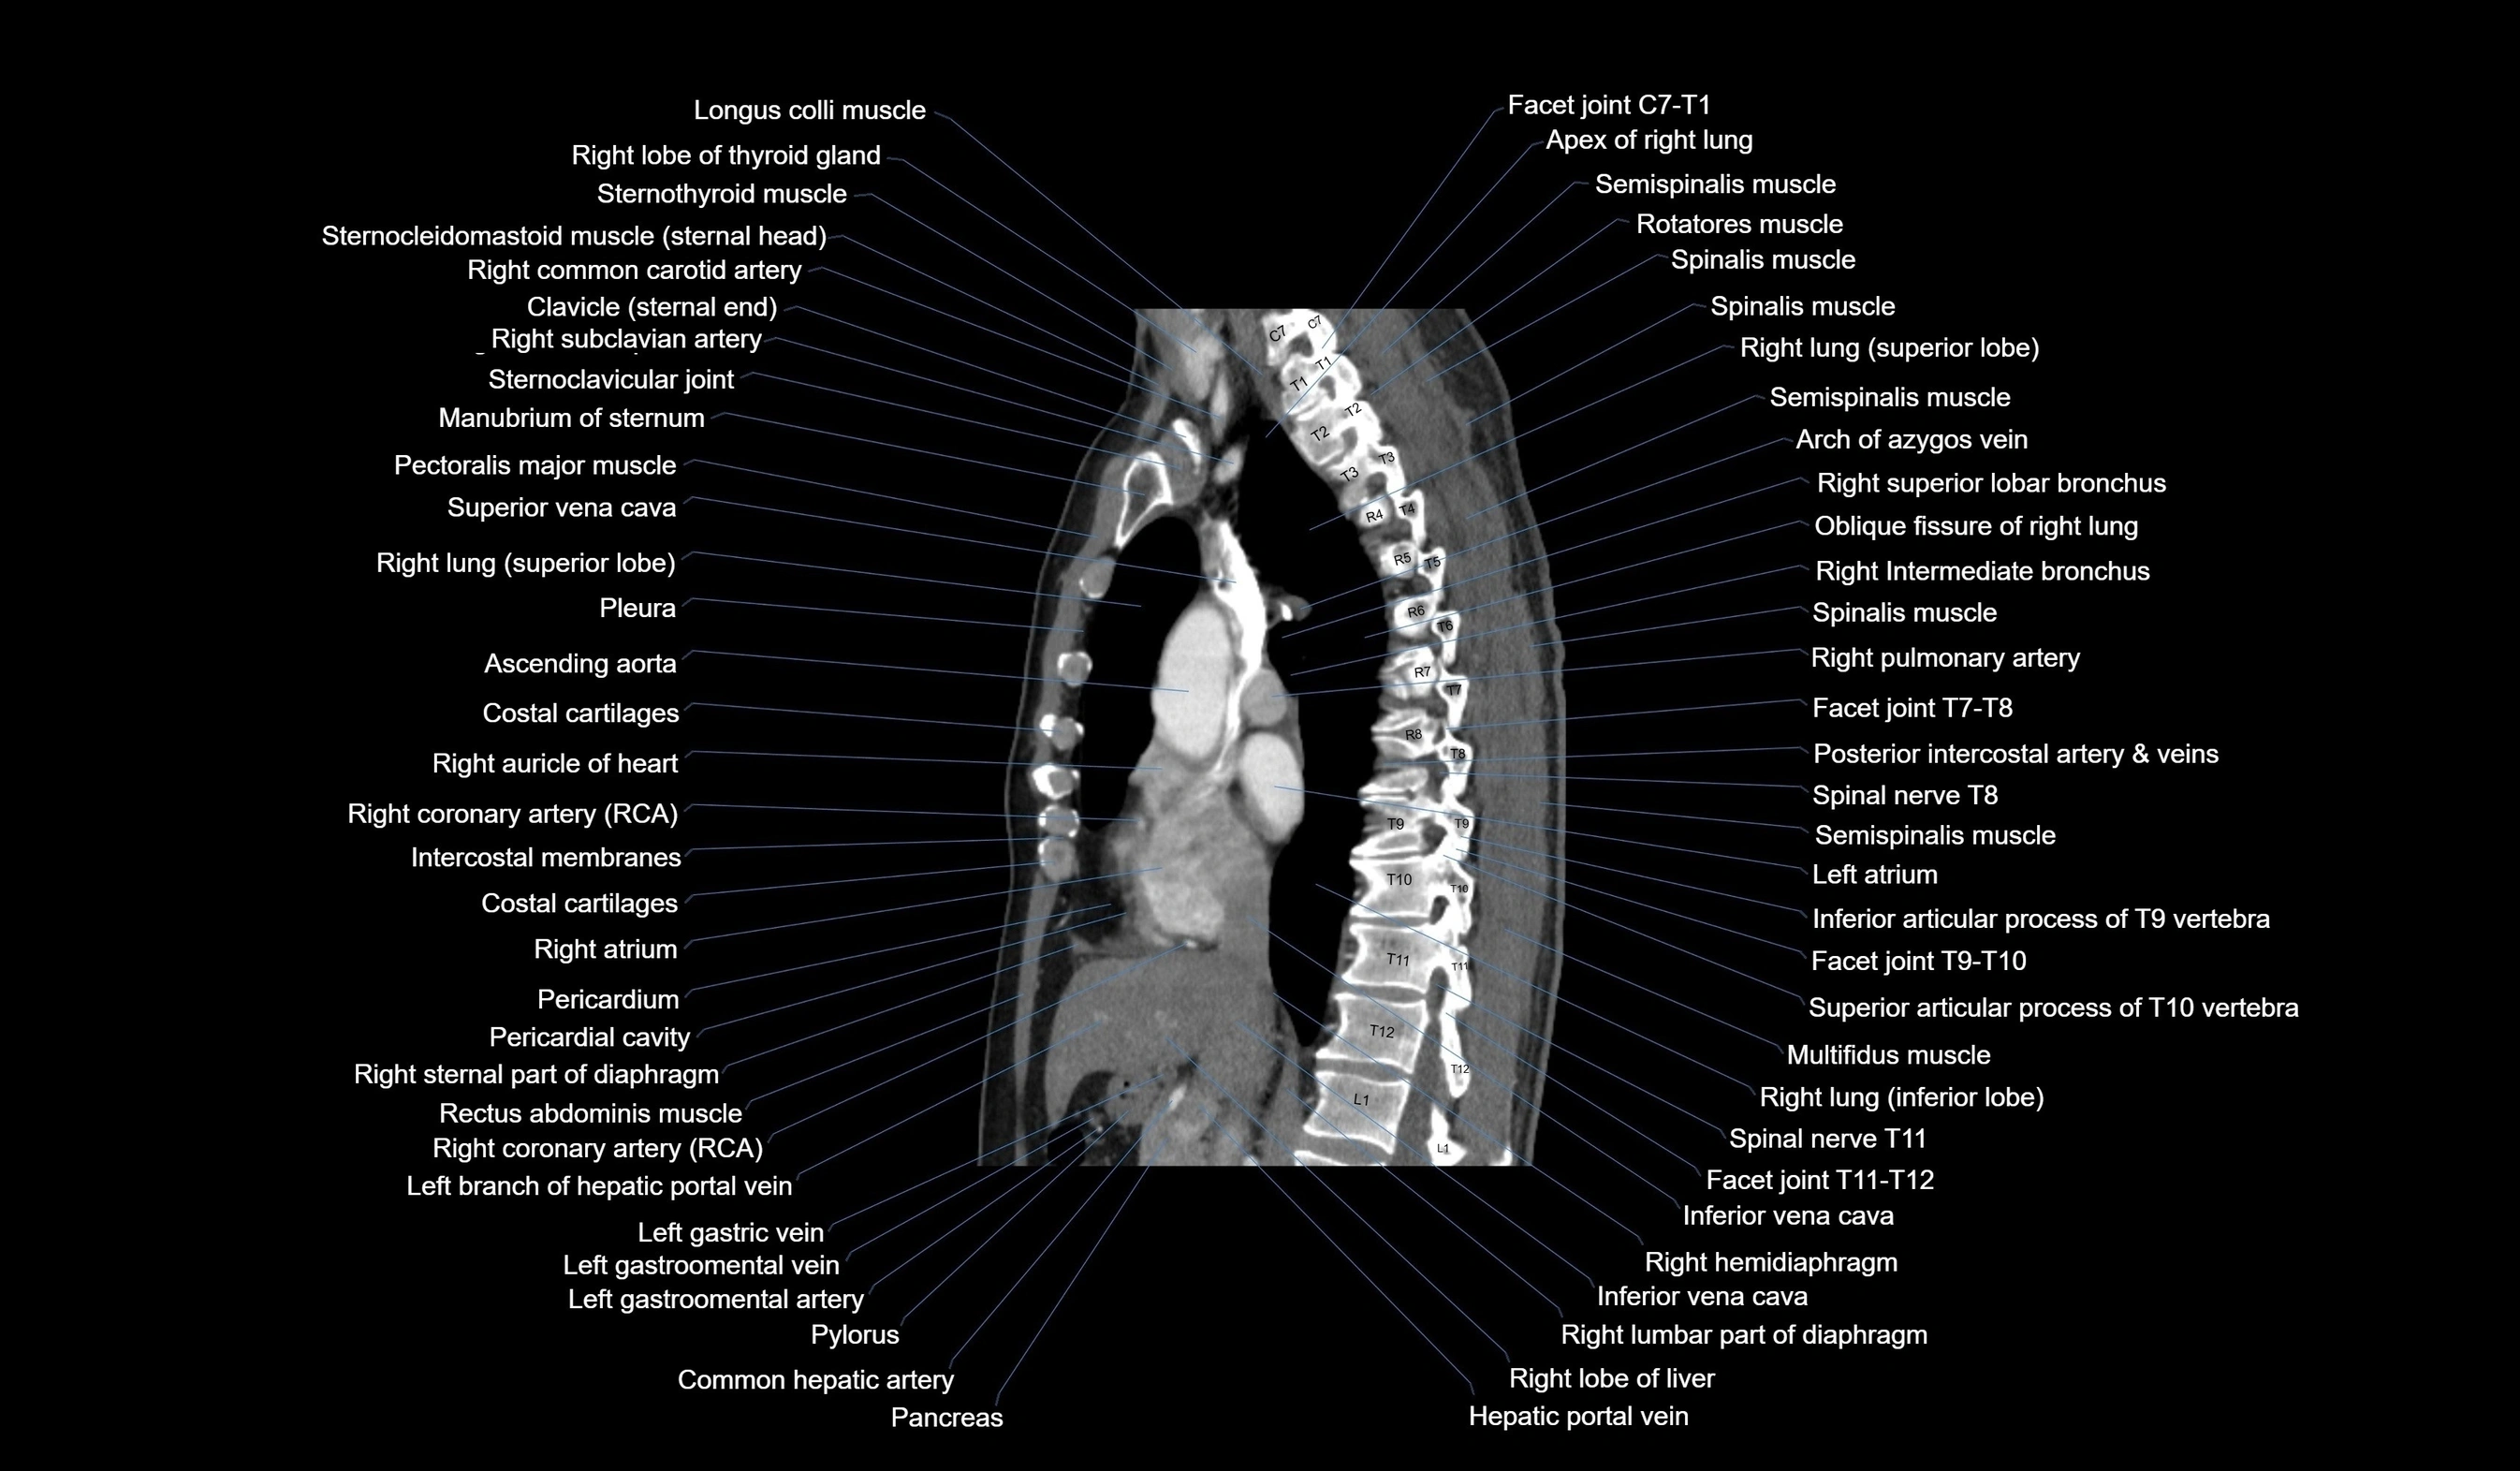

CT images